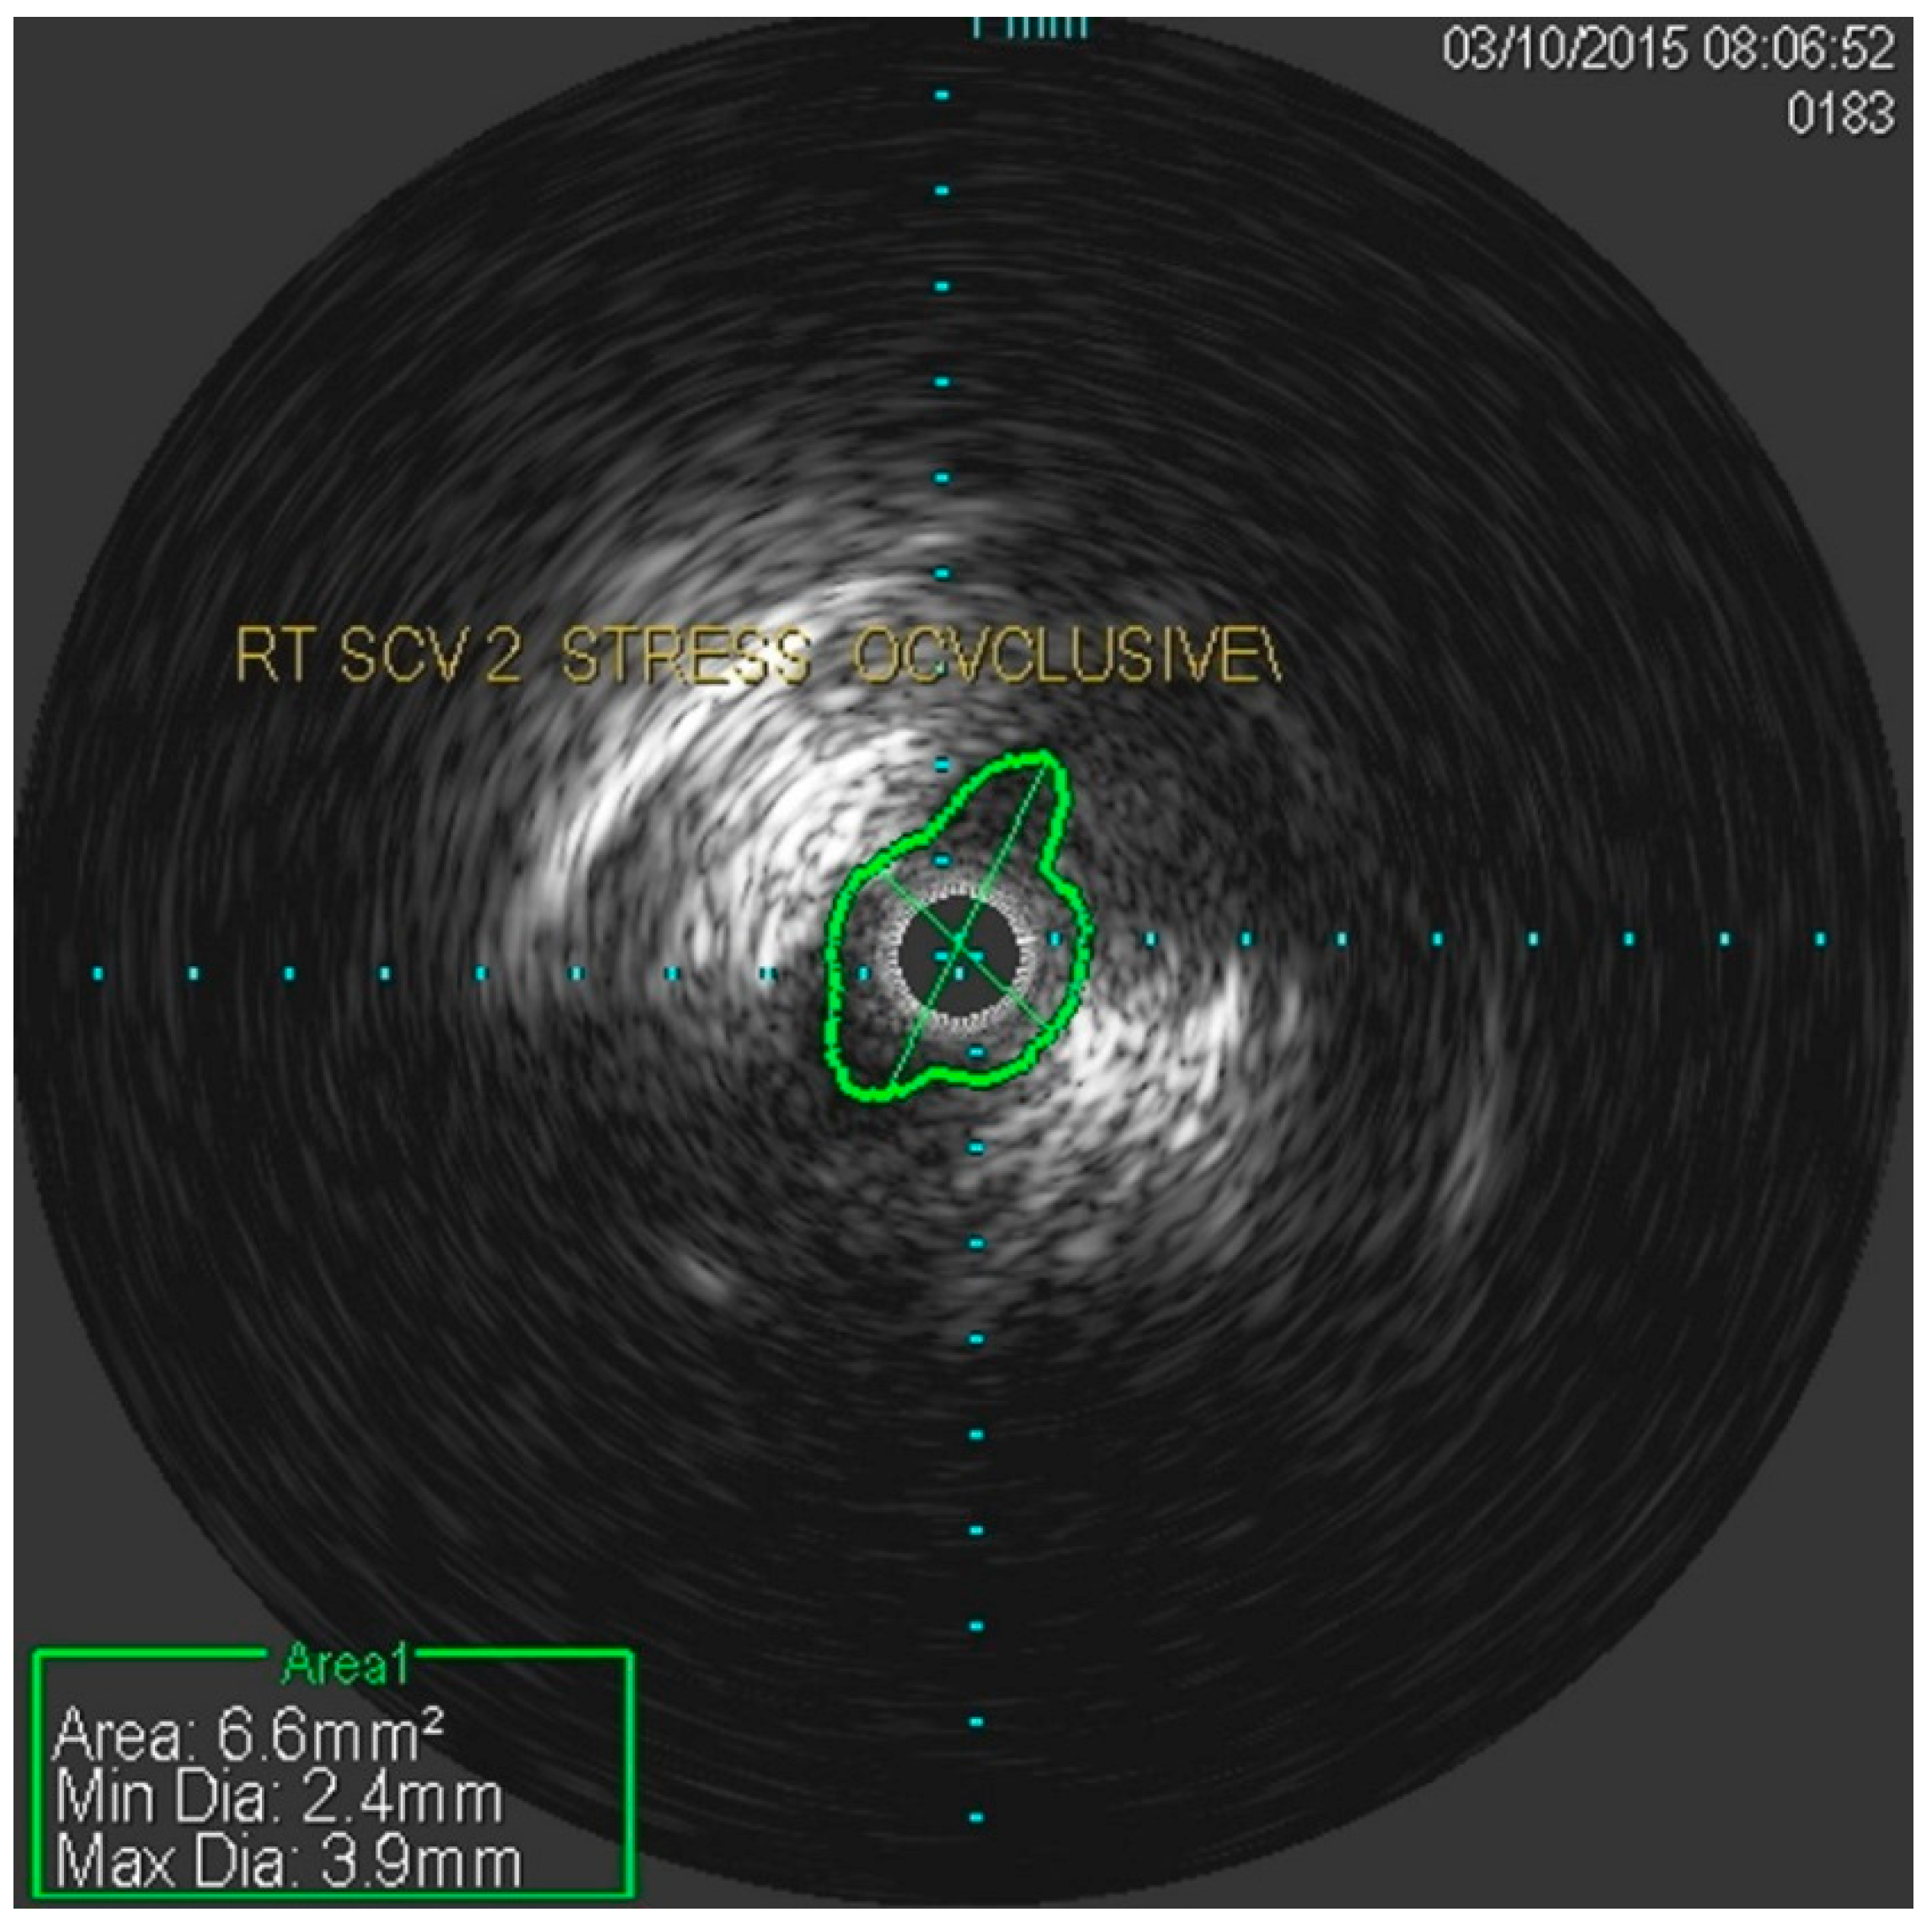

She underwent venography of the right arm venous system which revealed a 70–80% stenosis of the right subclavian vein in neutral position (Figure 1 and Figure 2). The vein was completely occluded in stress position. This was confirmed with intra-vascular ultrasound (IVUS). On IVUS measurements, the neutral position yielded a 74.4% stenosis while the stress position yielded 100% total occlusion (Figure 3 and Figure 4). It was noted that the contralateral vein appeared compressed in the costochondral space as well, though she was asymptomatic.

Figure 3.

Nearly occluded right subclavian vein in stress position as demonstrated by IVUS.